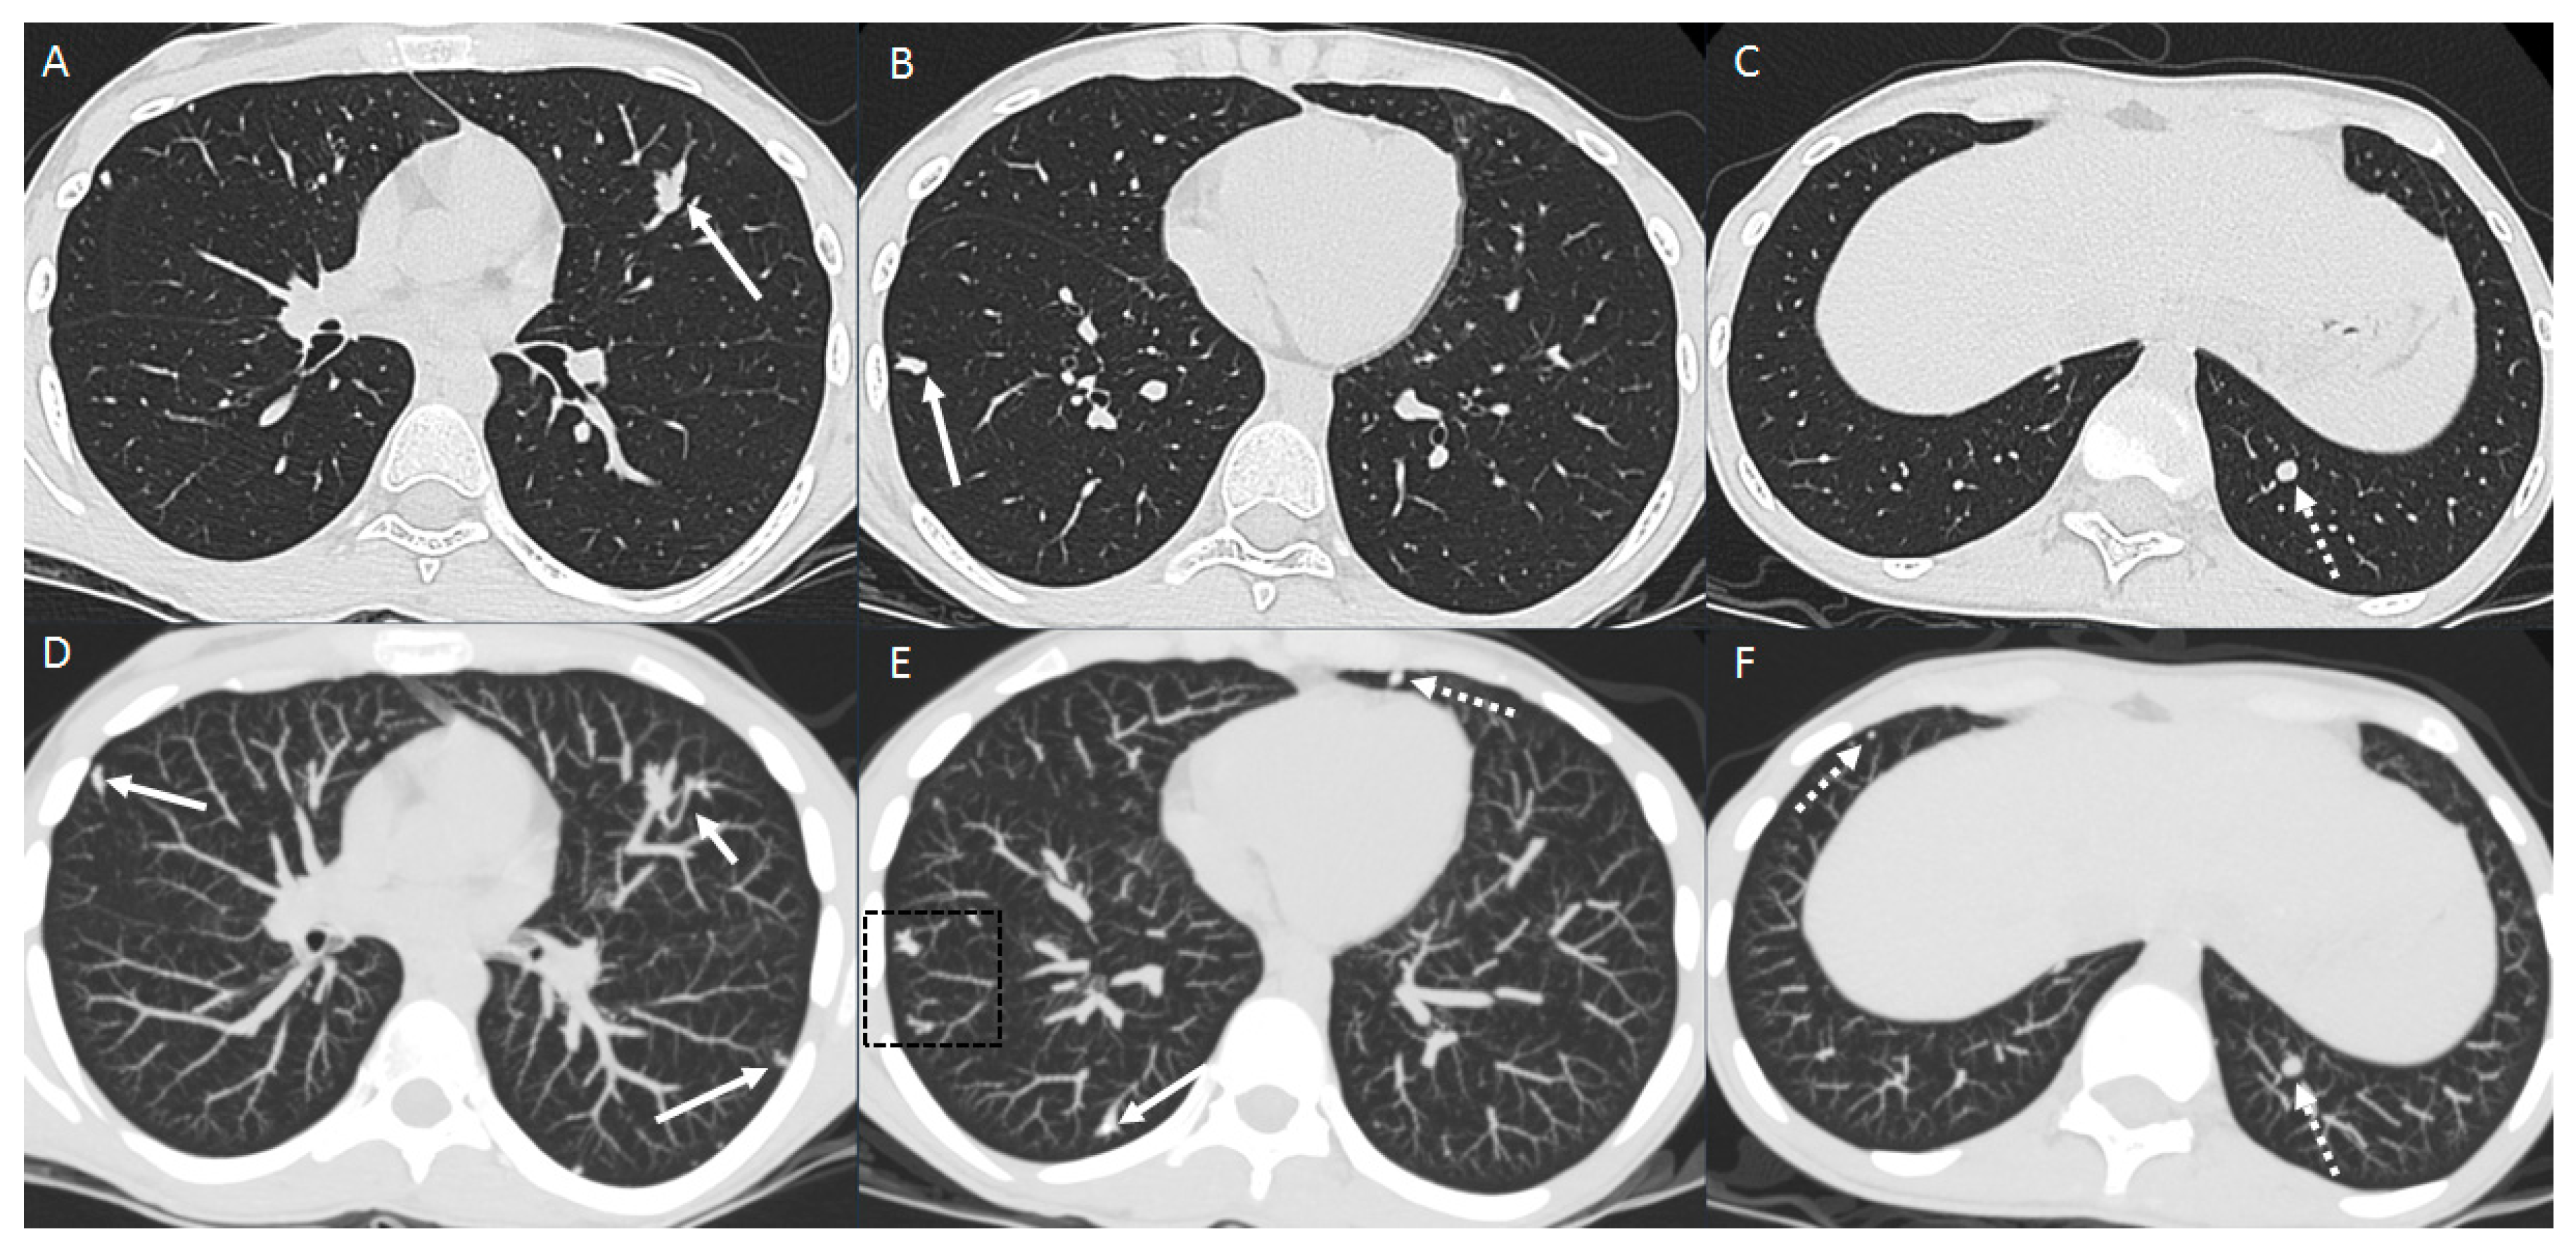

2. The Lungs

2.1. Parenchymal Metastasis

2.2. Vascular Metastasis

2.3. Endobronchial Metastasis

2.4. Lymphangitic Carcinomatosis